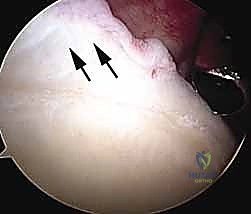

Clinical & Radiographic Imaging